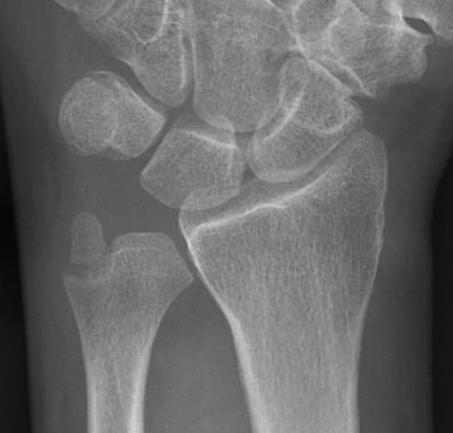

Classification ulna styloid process fractures

| Type 1: Tip fracture | Type 2: Base fracture |

|---|---|

|

Stable DRUJ

DRUJ potentially unstable |

![]() |

Ulna styloid process fracture and acute DRUJ instability

Ulna styloid fracture with TFCC injury